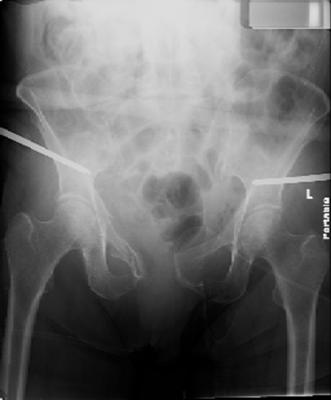

attached are images of a 70 year old female after peds versus car. her own car ran her over.

injuries are limited to the pelvis. left rami open and visible in a 10cm vertical laceration just lateral to left labia majora. wound is grossly clean. no vaginal and no urinary issues. CT scan shows widening of both SI joints anteriorly but I think this is vertically stable pattern.

pt treated that night with I/D and supra-acetabular frame to close the ring. consideration was given for SI screws bilateraly, but given time of night and other factors decision made not to proceed.